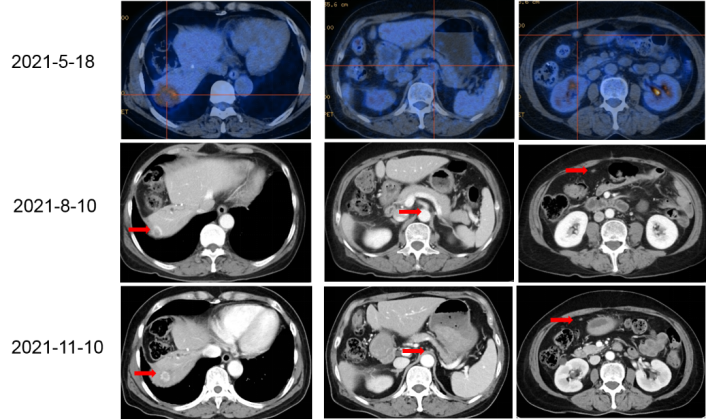

影像学检查:2021-5-18 我院PET-CT示结肠癌肝转移治疗后复查,1.结肠呈术后改变,吻合口局部未见明确恶性肿瘤征象;2.肝脏部分切除术后改变,肝右后叶稍低密度肿块,大小约4.3cm×3.8cm,代谢增高,考虑肝转移;3.上腹部腹膜后区增大淋巴结,较大者短径约1.0cm,代谢增高,考虑淋巴结转移;4.腹膜、系膜内多发软组织密度结节,较大者直径约1.3cm,部分代谢增高,考虑转移性病变。

患者于我院2021-6-9至2021-10-9 给予共7周期西妥昔单抗+奥沙利铂+雷替曲塞(q2w)方案治疗,2022-8-10 首次评估:肝脏及腹膜病灶明显缩小,腹膜后淋巴结消退,疗效评估均为:PR。

2021-11-10 再次评估时疗效持续PR(图一)。

△图一